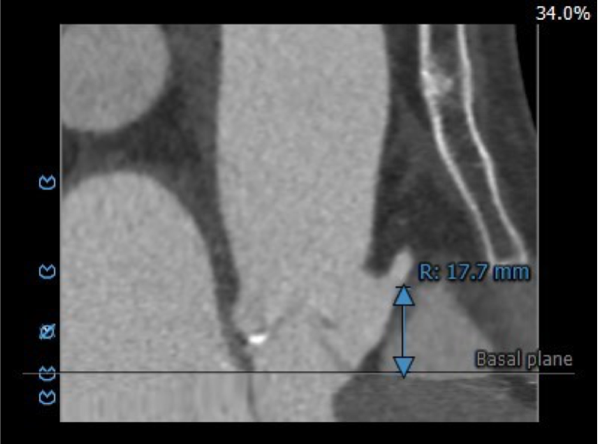

血管外周入路评估

腹主下段、双髂总附近多发钙化,部分截段钙化呈环状分布,血管内径受限,双侧股动脉穿刺点周围少量附壁钙化。